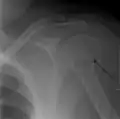

Proximal humerus fracture

A transverse fracture of the humerus shaft